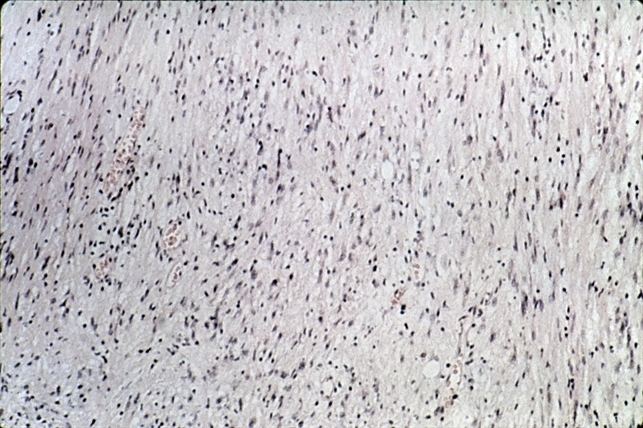

- Neurilemmoma. Antoni B pattern is composed of degenerated microcystoid areas of tumor (H&E xlOl).